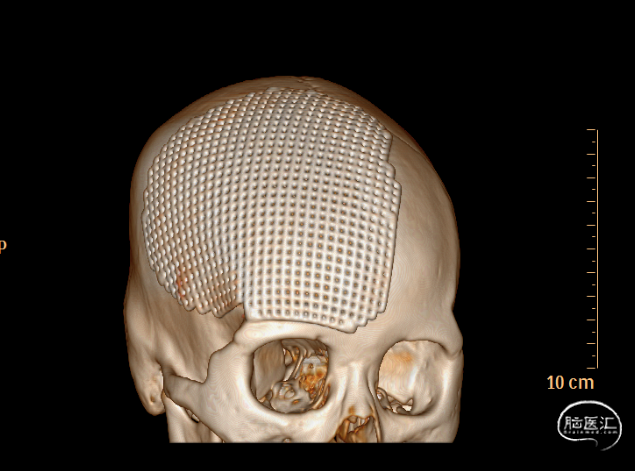

术后

术后CT